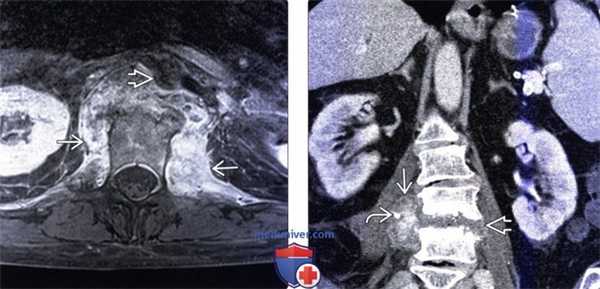

Рецидивирующие боли с повышением уровня маркеров воспаления (сепсис) после спондилодисцита. МРТ поясничного отдела позвоночника (сагиттальная проекция, Т2-взвешенное изображение). Двояковыпуклое эпидуральное объемное образование на уровне позвонка LIII. Образование дает равномерный сигнал повышенной интенсивности, оно отграничено от спинного мозга капсулой, дающей слабый сигнал. Повышена интенсивность сигнала от межпозвоночных дисков на уровне от LII- LIII до LIV -LV

МРТ позвонка LIII (горизонтальная проекция, Т2-взвешенное изображение). Абсцесс распространяется через левое межпозвоночное отверстие в большую поясничную мышцу слева.

МРТ позвонка LIII (горизонтальная проекция, Т1 -взвешенное изображение с подавлением сигнала от жировой ткани и контрастированием). Псоас-абсцесс и эпидуральный абсцесс.